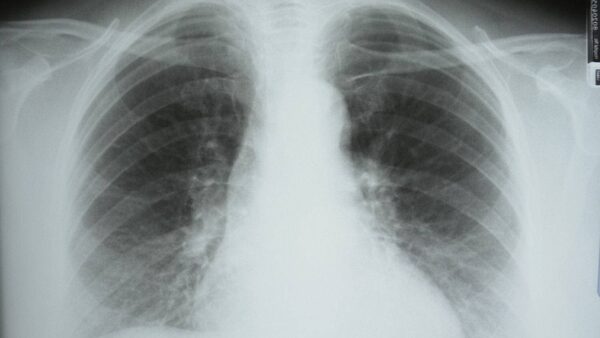

Chronic obstructive pulmonary disease, or COPD, is a progressive illness characterized by lung damage that makes it increasingly difficult to breathe. It is the fourth leading cause of death in Canada, and by 2030 the World Health Organization predicts it will be the third leading cause of death worldwide.

At least people are aware lung cancer exists. COPD lives mainly in the shadows, with many cases going undiagnosed and treatment not being effectively delivered. The disease sets in "almost imperceptibly, gradually depriving individuals of their health and vitality," says a 2010 report from the Canadian Thoracic Society.

Often, individuals are diagnosed with chronic bronchitis, a persistent cough or a respiratory-tract infection when, in fact, they have COPD. The years go by and the disease progressively worsens, to the point of increasing disability, lung attacks that land them in the hospital and, eventually, death.